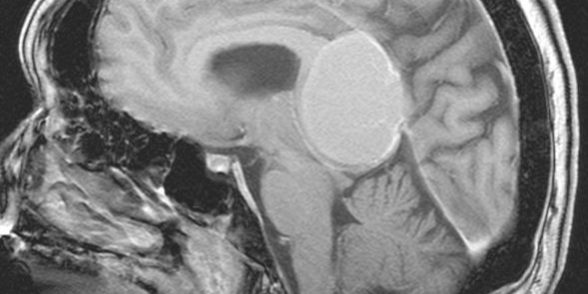

Ο απεικονιστικός έλεγχος με μαγνητική τομογραφία ανέδειξε ευμεγέθη όγκο στην περιοχή της επίφυσης (κωνάριο) με πίεση επί του μεσολοβίου, του τετραδύμου πετάλου και λοιπών εν’ τω βάθει δομών.

Διενεργήθη δεξιά ινιακή, διασκηνιδιακή, διαδρεπανική προσπέλαση και ολική αφαίρεση της βλάβης.

Η μετεγχειρητική αξονική τομογραφία εγκεφάλου δείχνει ολική εξαίρεση. Η ιστολογική εξέταση ανέδειξε μηνιγγίωμα (WHO I).